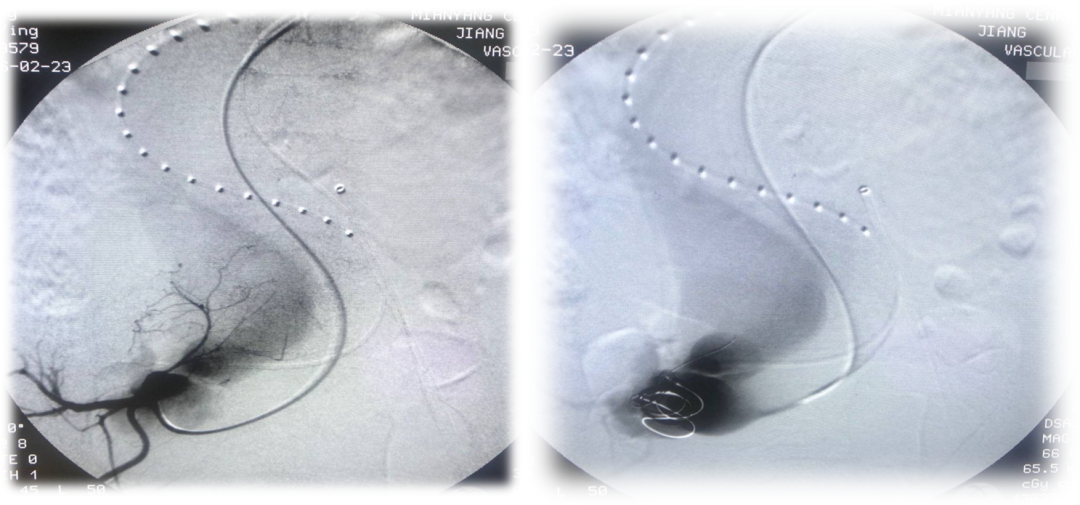

面对该患者的复杂病情,组织了多学科联合会诊,特别邀请张玮教授参与指导术前讨论,重点关注术中血压变化。考虑到当时的经济条件和手术方法,最终确定的手术方案为采用腔内修复术(EVAR)联合髂内动静脉瘘弹簧圈栓塞术,支架器材选用腹主覆膜支架+可控弹簧圈。

手术过程中,先进行髂内动脉栓塞,再实施腹主动脉EVAR手术。